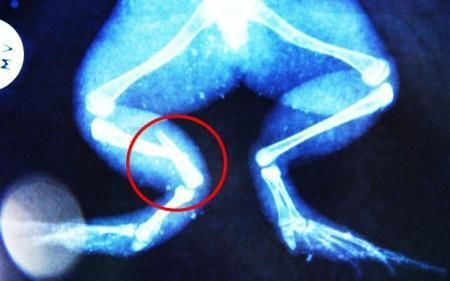

環(huán)球網(wǎng)4月2日報道 據(jù)《每日郵報》報道,上個月,南非大牛蛙布魯萊的右小腿被鄰居家的一只狗咬到,導(dǎo)致粉碎性骨折,現(xiàn)在經(jīng)過2個小時的手術(shù),它的斷腿已經(jīng)被接上,它也因此成為有史以來第一只通過外科手術(shù)用鋼針接上斷腿的青蛙。

野生生物專家安妮經(jīng)常為學(xué)校寫教材,她認(rèn)為這是人類第一次通過手術(shù)給一只青蛙接斷腿。在手術(shù)開始階段,獸醫(yī)把少量給狗用的麻醉藥注入到這只青蛙體內(nèi),讓它失去知覺。然后他在布魯萊的斷腿上切開一個小口,把一根小鋼針植入腿里。最后獸醫(yī)給它縫了9針,把切口縫合在一起。僅僅幾周后,布魯萊就能在安妮家附近活動了。這只青蛙大約已有25歲,主要以嚙齒動物、蛇和其他青蛙為食。布魯萊所屬的牛蛙種群正在不斷減小,目前只能在非洲南部的濕地里才能看到這種青蛙。